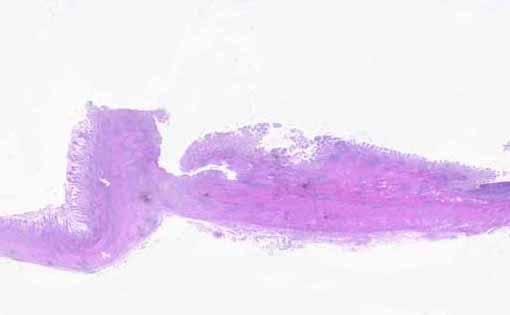

다른 병원으로부터 진행암을 의심받았으나、주병변의 형태와 소장측의 2개의 위성병변으로부터、수술 전에 단순성궤양으로 진단된 예

염증성 및 궤양성질환/단순성궤양

마이크로